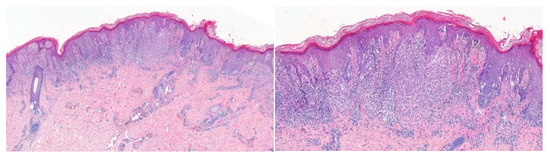

Figure 2.

2-year-old male, left buttock–Atypical Spitz Tumor; left: compound atypical melanocytic proliferation composed of spindle and epithelioid melanocytes; right: confluent irregular nests with solid growth of melanocytes associated with a brisk lymphocytic infiltrate.